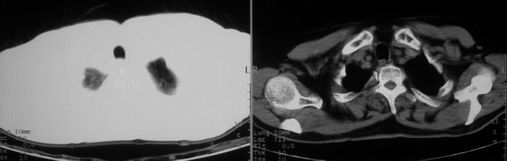

男,78岁,咳嗽、咳痰、发热入院,抗炎治疗一周后已退热,咳血似痰。

10月3日片:

ct左肺下叶大片状高密度影,病变密度不均,界限不清,左侧胸腔积液,治疗后复查临床症状好转而影像学表现病变有发展,还是首先考虑感染性病变,复查时间短附合感染性病变的病理改变。